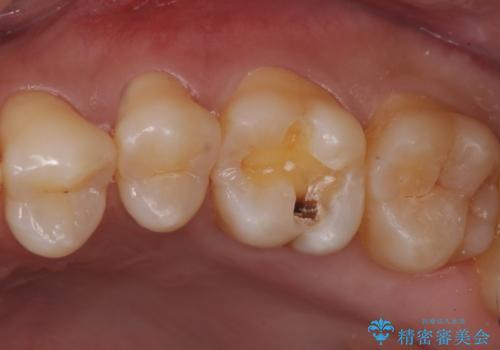

検査の結果、昔治療した樹脂の詰め物と歯の間に虫歯ができていることが確認されました(二次う蝕といいます)。

同じような樹脂の詰め物での治療ではまた虫歯ができることが予想されるため、今回はセラミックインレーで修復することとなりました。

視診だけではわかりづらいですが、レントゲン画像にて昔の詰め物の下に虫歯があることがわかります。

以前樹脂を詰めた結果再び虫歯ができてしまっていることから、同じ治療は同じ結果になる可能性があるため今回はアプローチを変えてセラミックインレーで修復処置をしていくこととなりました。